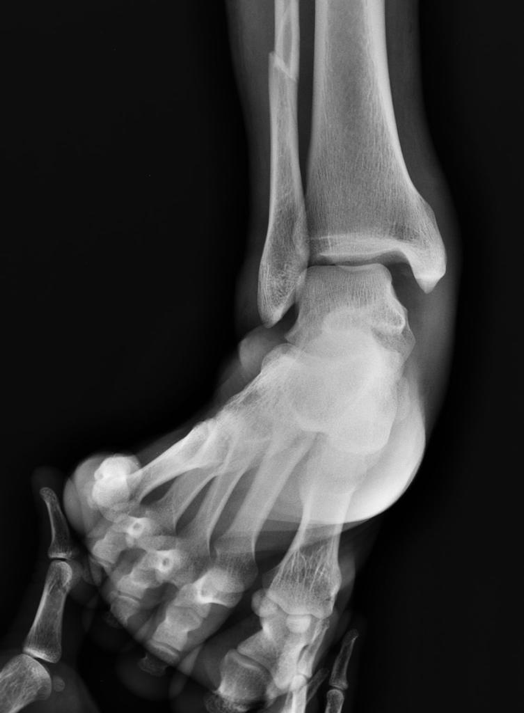

- Views

- Standard three views (AP, Lateral, Mortise)

- Varus stress view